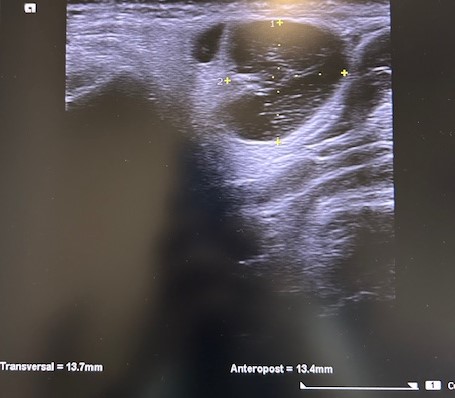

Eco-PAAF: lesión sólida de morfología nodular posterior al ángulo mandibular derecho, con medidas aproximadas de 15 x 21 mm. Presenta ecoestructura heterogénea con áreas quísticas en su interior y con vascularización en el estudio Doppler.

PAAF: celularidad epitelial oncocítica sin atipias, formando grupos y con abundante celularidad linfoide y granular, pudiendo estar en contexto de un tumor de Warthin.